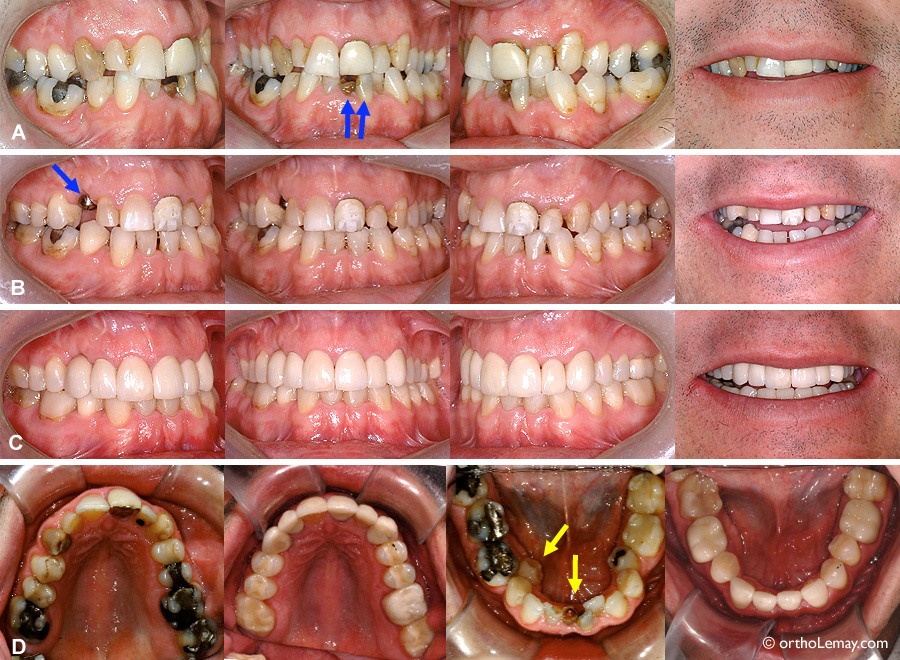

Caractéristiques du cas PB

Homme de 44 ans avec dentition mutilée ayant requis une intervention en orthodontie, parodontie, chirurgie, endodontie et prosthodontie.

(A) Avant l’orthodontie; les incisives centrales inférieures (flèches) ont un traitement de canal et celle de droite est fracturée au niveau de la gencive.

(B) À la fin de l’orthodontie. La canine supérieur droite fut extraite pendant le traitement car elle était infectée et avait une perte osseuse importante autour de sa racine. Un implant dentaire fut posé (flèche).

(C) Après la phase prosthodontique; plusieurs facettes et couronnes furent faites pour redonner de bonnes proportions et améliorer l’esthétique.

(D) Vues occlusales des deux arcades avant le traitement d’orthodontie et après la pose des restaurations finales.